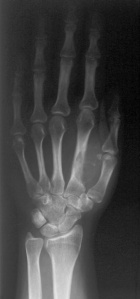

M.S. - 31 year old female complains of pain in her right first web space and index finger; pain began six months ago, but x-rays were not taken until recently since the patient was pregnant